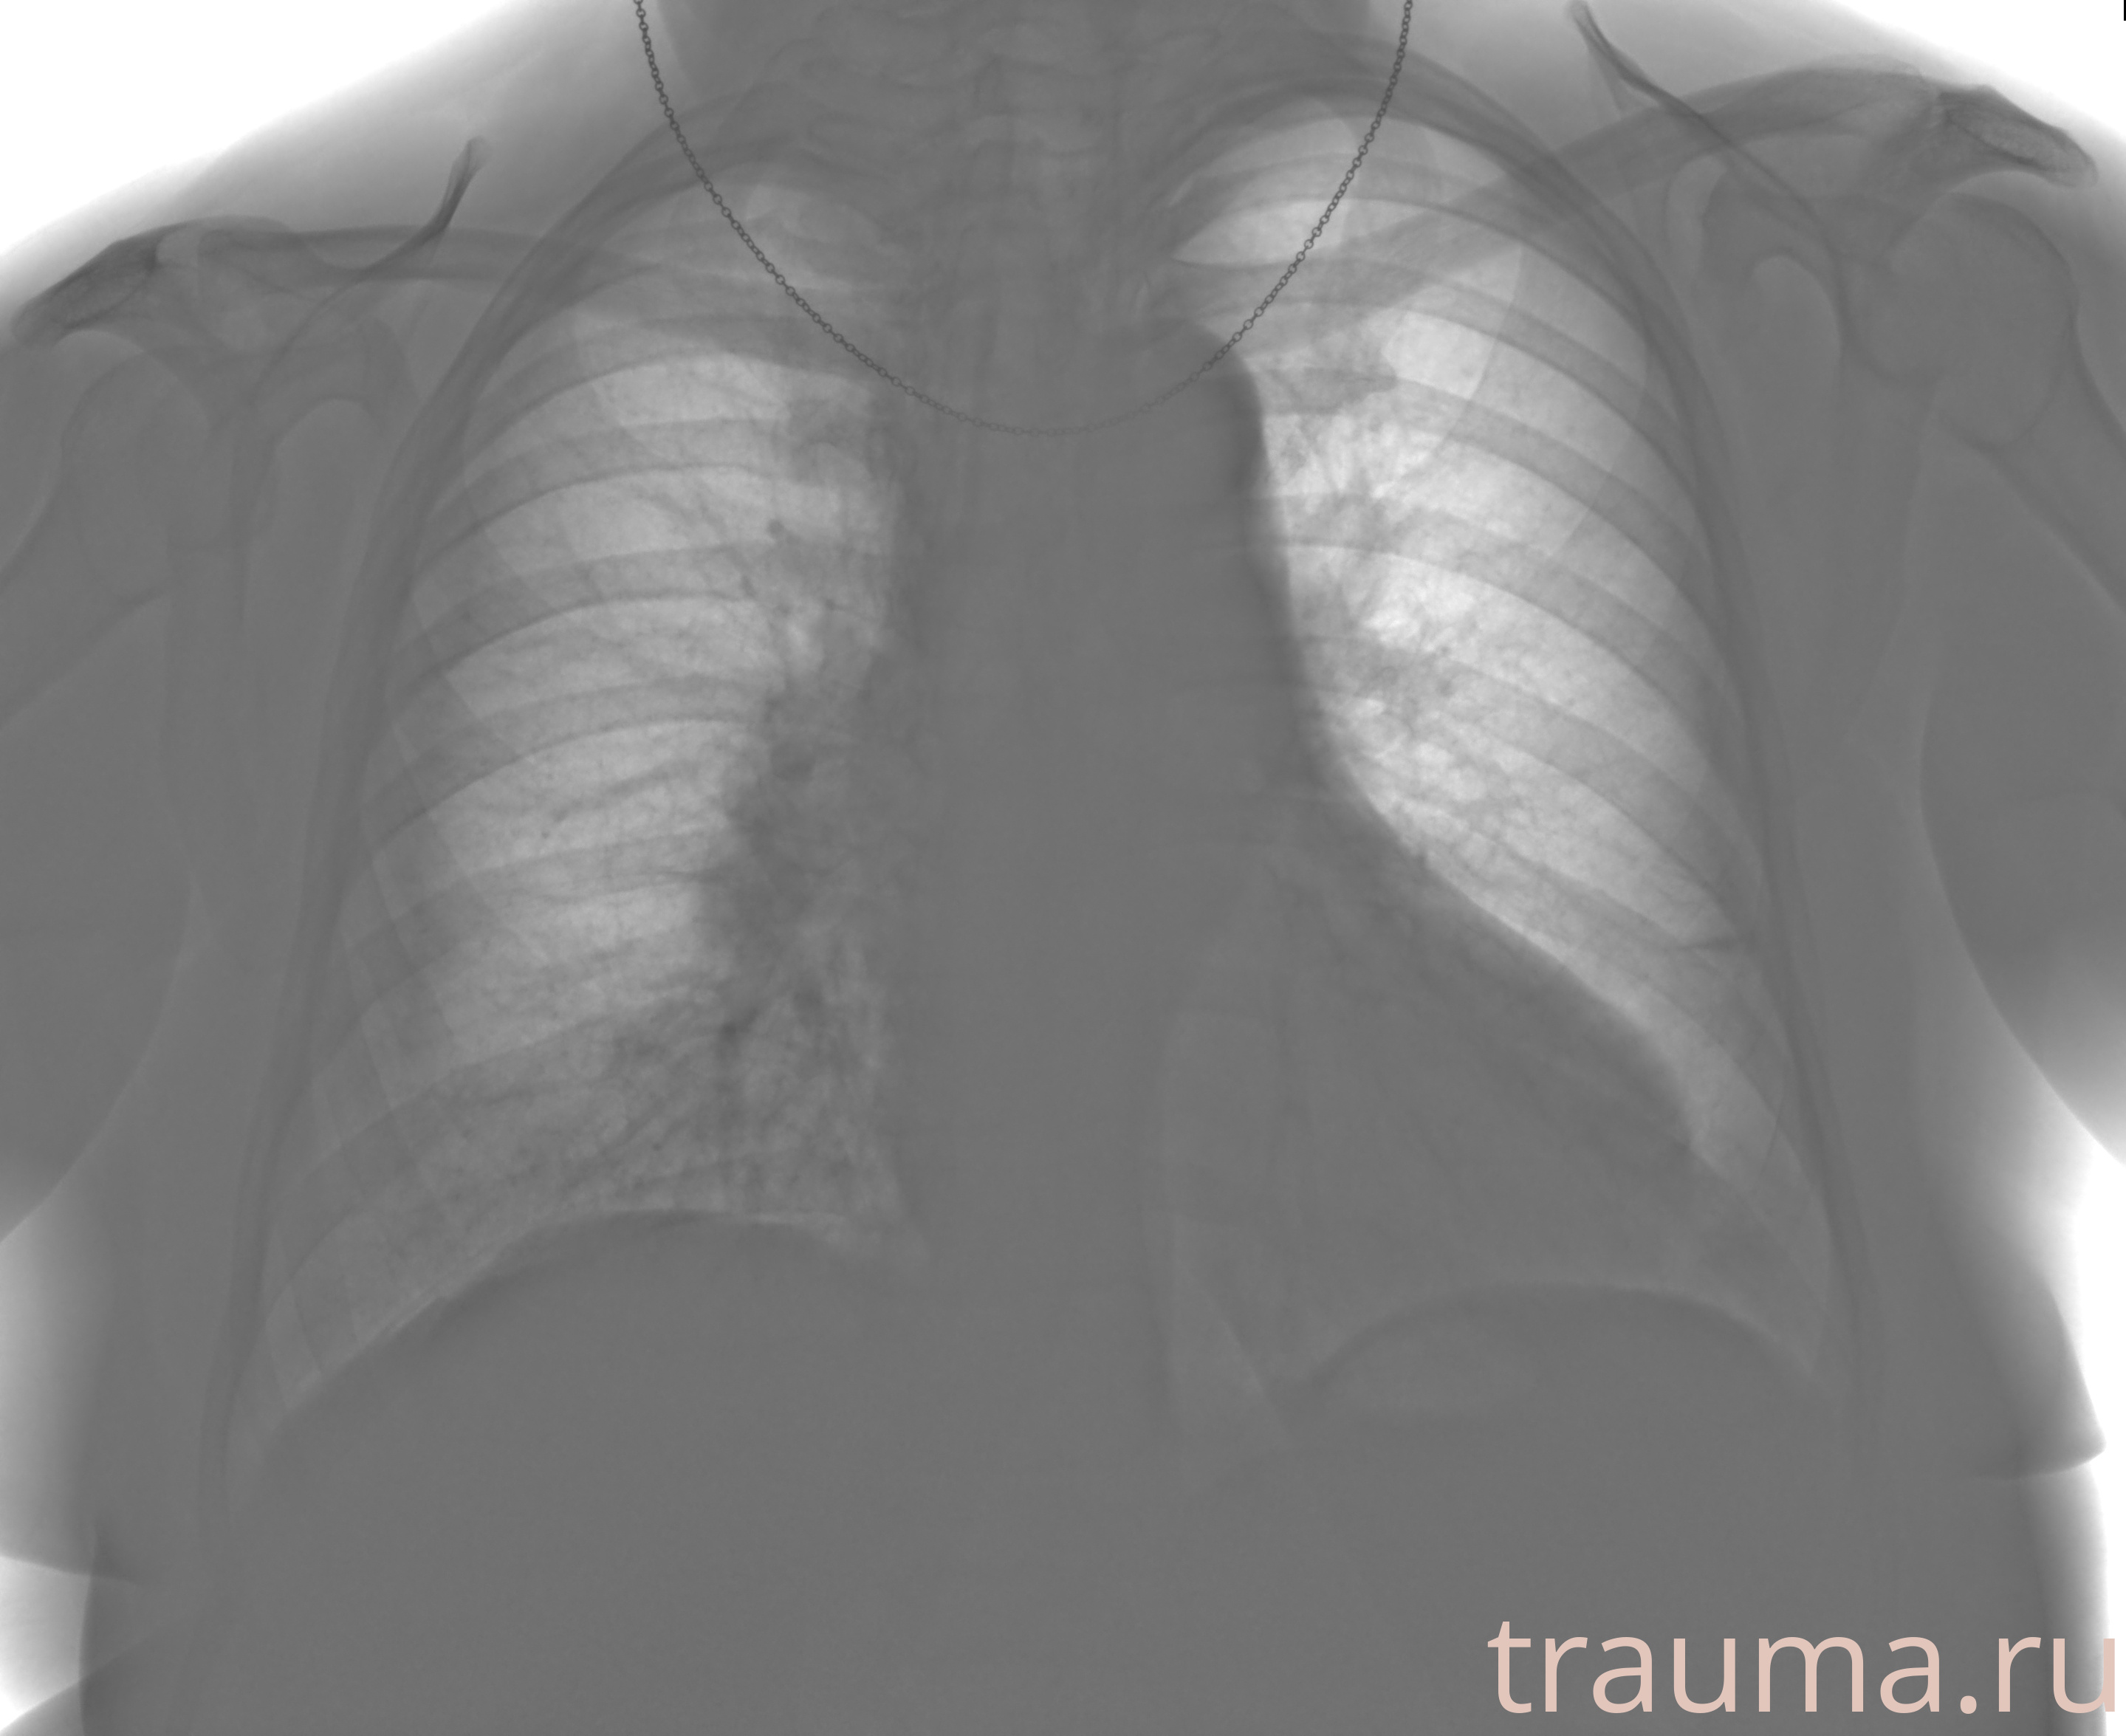

Рентген на дому: по вашему адресу приезжает врач-рентгенолог, травматолог-ортопед с мобильным рентгеновским аппаратом, проводит диагностику травмы или заболевания, делает необходимые рентгенограммы, дает рекомендации по дальнейшему лечению. Получить качественные снимки в домашних условиях возможно благодаря уникальной методике, разработанной МосРентген Центром для института  Склифосовского